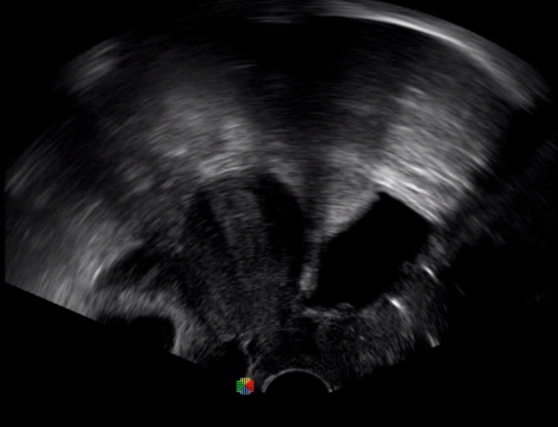

TEE(經食道超聲心動圖)將超聲探頭置入食道內,從心臟的后方向前近距離探查其結構 ,克服了經胸超聲檢查的局限性,避免肺內氣體、胸壁脂肪、胸廓畸形等因素影響,觀察角度更多,圖像更加清晰,測量數據更準確。

經食道超聲 大動脈短軸